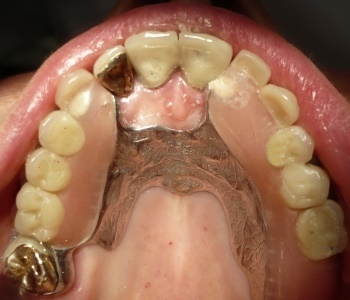

V zgornji čeljusti smo na edinem preostalem zobu izdelali konusno prevleko, ki skrbi za boljšo stabilizacijo proteze. |

Implantat s polzilom je v brezzobem delu čeljusti bistveno povečal podporno polje proteze. |

Vstavljena delna proteza. |